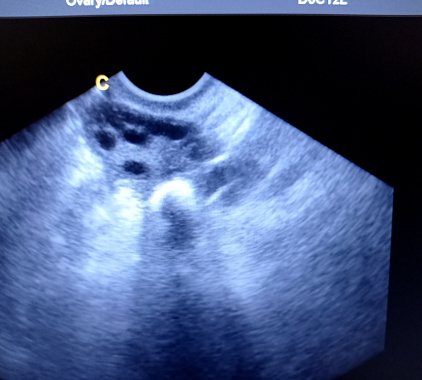

На УЗ-диагностике удается оценить размеры органов, положение, границы, отношение я рядом расположенным тканям, подвижность, наличие включений, их плотность и так далее. Состояние яичников зависит от дня цикла и возраста женщины. Изначально в норме размеры придатков у молодых девушек одинаковые. Соответственно, если увеличены яичники на УЗИ, следует провести дополнительные обследования для выяснения причины. К 35-40 годам размеры уменьшаются. В норме контуры органа бугристые, просматривается 9-10 фолликулов размером до 5 мм.

Возможны следующие отклонения в описании на УЗИ – рак яичника, кисты, поликистоз, увеличение или уменьшение размеров, внематочная беременность, желтое тело (указывает на беременность) и так далее.

Фотогалерея